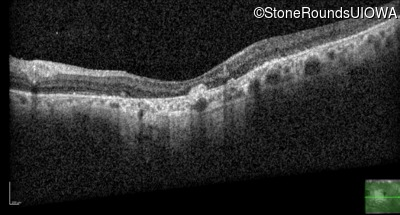

Optical Coherence Tomography - Right - 20/125 -2

Exemplar / OCT Stack

OCT Stack